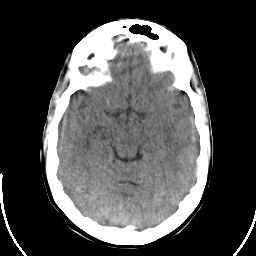

Sarcoma: Roentgen-ray CT -- Slice #9

[Home][Help][Clinical] Slice 9